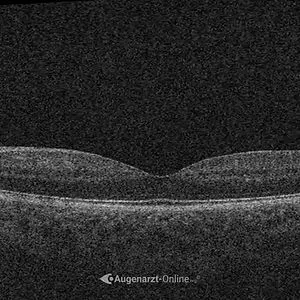

Lebensstil

Bei einer frischen, akuten Chorioretinopathia Centralis Serosa ist nicht immer sofort eine Behandlung nötig. In vielen Fällen bildet sich die Flüssigkeit unter der Netzhaut innerhalb von Wochen bis wenigen Monaten von selbst zurück. Deshalb wird zunächst oft eine engmaschige Kontrolle mit OCT empfohlen. Gleichzeitig sollten mögliche Auslöser (Kortison, Stress, ...) gemieden werden.

Wurde bei Ihnen eine Chorioretinopathia Centralis Serosa festgestellt, sind regelmäßige augenärztliche Kontrollen wichtig, um die Entwicklung des Befunds im Blick zu behalten. Dabei werden Veränderungen der Makula mit OCT-Aufnahmen dokumentiert und die Sehschärfe überprüft. So lässt sich erkennen, ob sich die Flüssigkeit unter der Netzhaut zurückbildet oder ob die Erkrankung weiter besteht.

Die Behandlung richtet sich nach dem Verlauf der Erkrankung. Bei einer akuten Chorioretinopathia Centralis Serosa reicht zunächst oft eine engmaschige Kontrolle, da sich die Flüssigkeit unter der Netzhaut häufig von selbst zurückbildet. Bleibt der Befund bestehen oder tritt die Erkrankung wiederholt auf, kann eine gezielte Therapie notwendig werden.